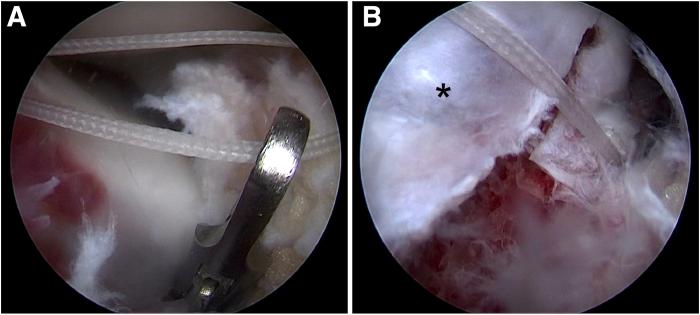

Few cases of anterior cruciate ligament (ACL) tibial avulsion injuries occur in adolescents. Bony ACL avulsion from the tibial side has been treated by various methods ranging from conservative management to a wide range of operative procedures. Various arthroscopic operative procedures are available to reduce and fix these fractures. We describe a technique of arthroscopic "8" knotted fixation without any tibial tunnels for tibial-sided ACL avulsion. This simple technique avoids the potential complications of hardware fixation within a joint. It represents an arthroscopic treatment option for ACL tibial avulsion injuries.

青少年前交叉韧带(ACL)胫骨撕脱伤的病例很少见。从保守治疗到广泛的手术操作,胫骨侧ACL骨撕脱伤有多种治疗方法。有多种关节镜手术可用于复位和固定这些骨折。我们描述了一种关节镜下“8”字打结固定技术,用于胫骨侧ACL撕脱伤,无需任何胫骨隧道。这种简单的技术避免了关节内硬件固定的潜在并发症。它代表了一种治疗ACL胫骨撕脱伤的关节镜治疗选择。